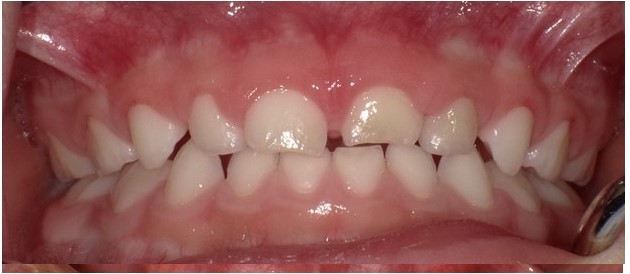

歯周疾患は歯肉炎と歯周炎に分かれますが、子どもで遭遇するのはほとんどが歯肉炎であり(図8)、歯周炎は極めて稀です。つまり、適切な口腔衛生指導を実施し、歯面清掃や歯石除去を行うことで、ほとんどのケ—スで容易に健全な歯周状態に戻すことができます。保護者によっては、家庭で歯石を取り除こうと一生懸命歯磨きをされることがありますので、歯科医院で専門的な器具を用いないと除去できないことを理解してもらってください。

(図8)歯肉炎の一例(4歳6か月男児)全顎的に歯肉の腫脹が認められる。